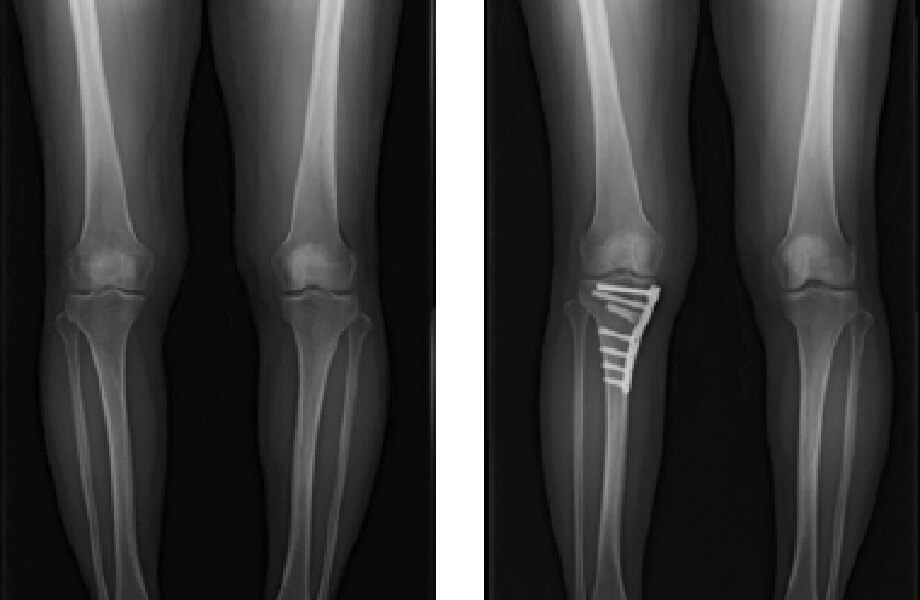

変形性膝関節症について

膝の軟骨がすり減り、体重がかかる部分の骨に負担がかかり痛みや変形を生じます。原因は加齢によることが多いですが、肥満も関与しています。また骨折、靭帯損傷や半月板損傷などの外傷の後遺症として発症することもあります。

症状は、立ち上がり・歩きはじめなど動作の開始時の痛みですが、末期となると歩行時の痛みが強くなり、歩行など日常生活が不自由になります。筋力訓練や装具、薬やヒアルロン酸の注射など保存的治療では効果がない場合は手術を検討します。 手術の方法としては、主に、人工膝関節置換術と高位脛骨骨切り術を行っています。人工膝関節置換術

O脚のため内側に偏った荷重時のストレスを比較的健常な外側に移動させる手術です。

比較的変形が少なく、スポーツ活動など比較的活動性の高い中高年の方が対象になります。

近年は手術機械や手技の進歩により、人工関節置換術と同程度の入院期間で自宅に退院できるようになってきています。 -